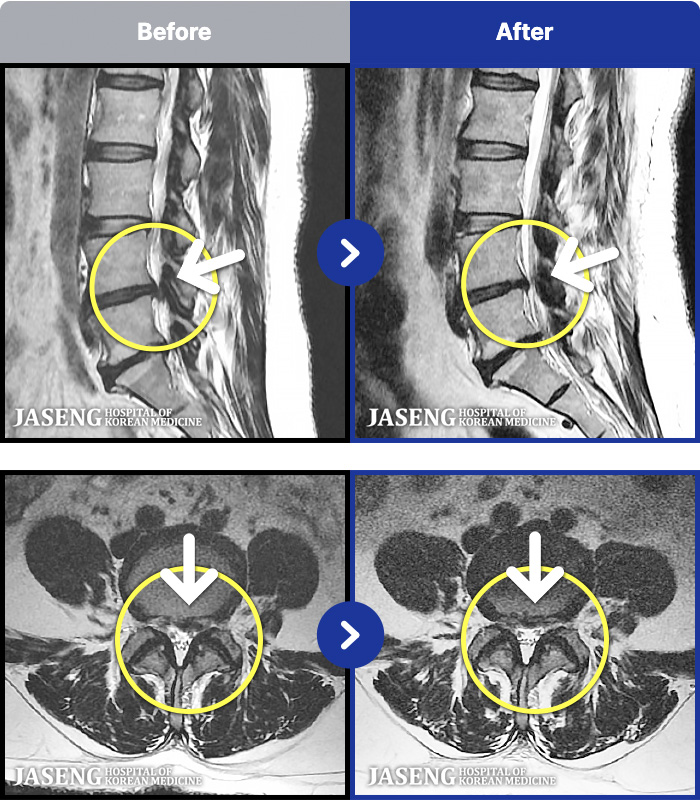

1,257 MRI ũ ʸ Ȯϼ.